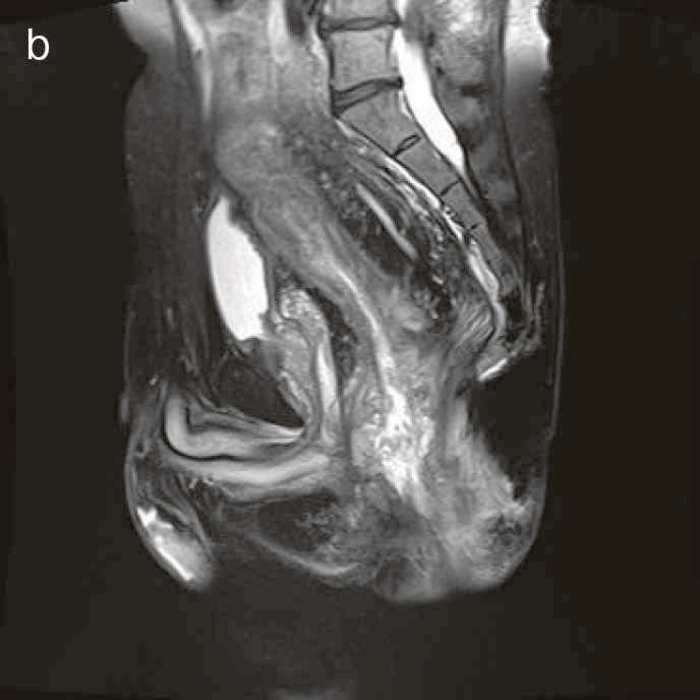

図41 腹部骨盤MRI

診断時のMRIでは直腸下部壁内から周囲にhigh intensity areaが拡がり,右側には痔瘻の瘻管を認めた。high intensity areaは前方で前立腺や陰茎海綿体付近まで広がっていた。